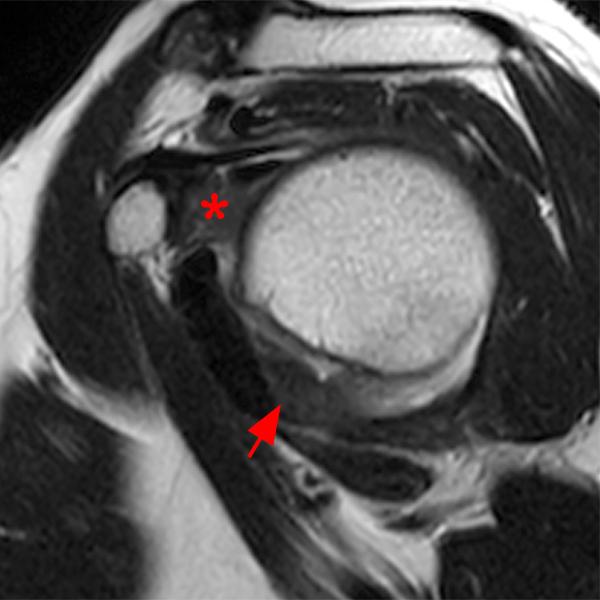

Adhesive capsulitis shoulder Image

from radiopaedia.org